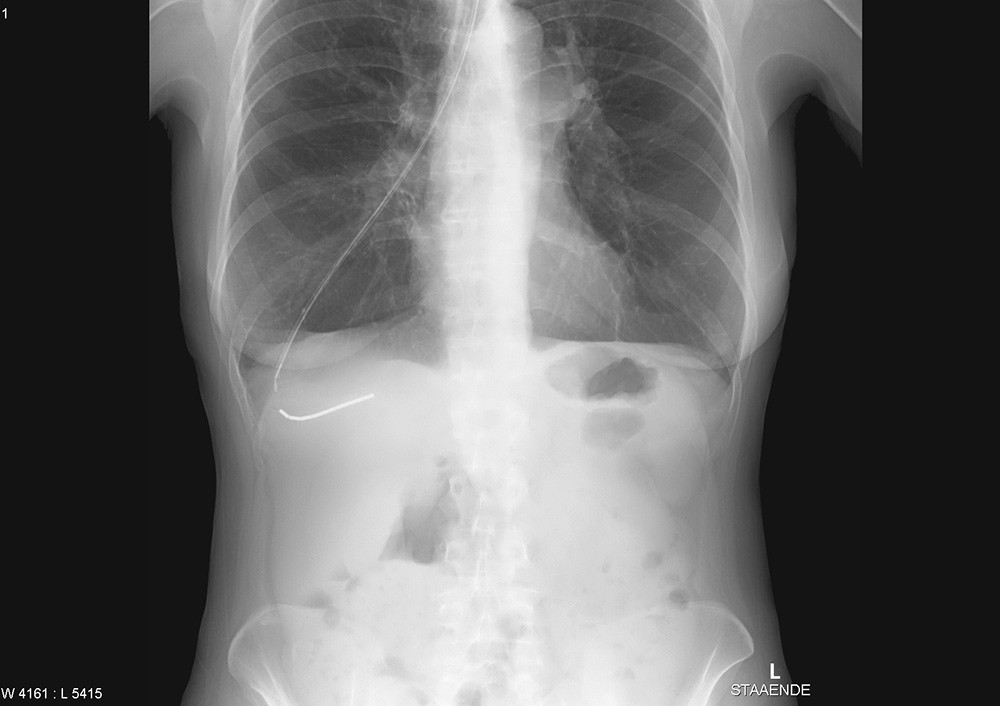

En kvinne i 60-årene var innlagt med svelgevansker og ernæringsproblemer. Hun var fra tidligere diagnostisert med supraglottisk plateepitelcancer og behandlet med utvidet strålefelt mot halsen og med cytostatika. Ved denne innleggelsen fikk hun lagt ned en tynn nasogastrisk sonde. Sonden hadde ytre diameter 1,95 mm og en stålmandreng. Den lot seg tilsynelatende føre ned ukomplisert. Ved instillasjon av 10 ml luft hørtes ikke bobler som normalt over magesekken. Røntgen av nedre thorax og øvre abdomen viste at sonden hadde fulgt bronkialtreet langt ut i høyre lunge (bilde til venstre). Sonden ble fjernet, men kort tid etter fikk kvinnen store pusteproblemer og stansalarmen måtte aktiveres. Røntgen thorax viste en stor høyresidig pneumothorax (bilde til høyre). Den ble vellykket behandlet med kirurgisk anlagt pleuradren.